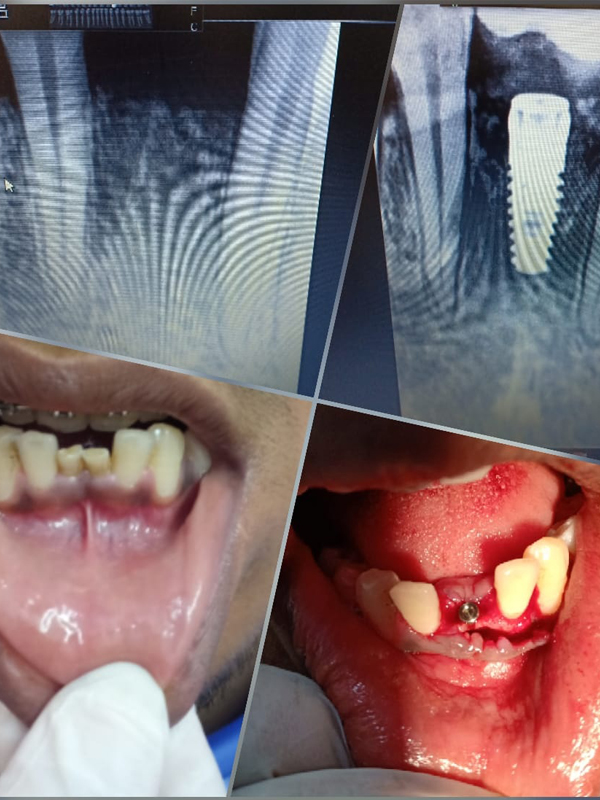

Home / Treatment Photos